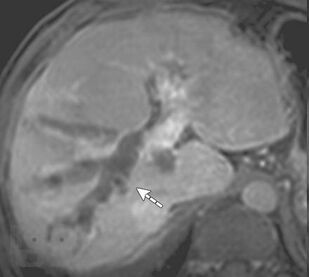

Неотложная хирургия - одно из наиболее актуальных, сложных и ответственных направлений хирургии. Пациенты пожилого и старческого возраста с механической желтухой различной этиологии толстой кишки составляют значительный контингент, госпитализируемый в хирургические стационары по экстренным показаниям. Издание реализовано с учетом опыта сотрудников кафедры и современных представлений о патогенезе, методах эндоскопической диагностики, клинических проявлениях и основных принципах лечения больных синдромом механической желтухи, обусловленной осложнениями патологии гепатопанкреатодуоденальной зоны и желудочно-кишечного тракта. Успех в лечении таких пациентов во многом зависит от своевременности и точности постановки диагноза.